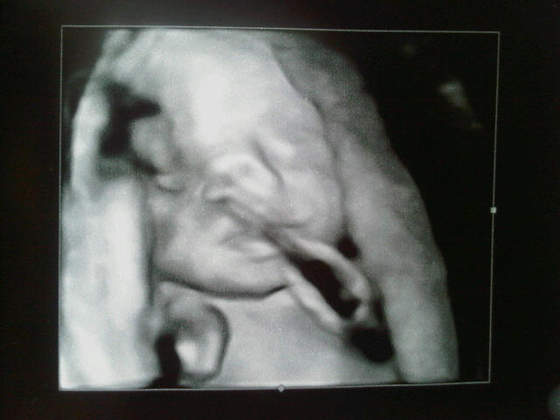

Zobacz załącznik 423947Zobacz załącznik 423948

Na piewszym pepowina wciela sie w kadr, a na drugim dzidzius nad czyms mysli ostro ;-)

Tak się złośliwiec ustawia, że buzię za każdym razem odwraca albo zasłania rączkami, za to siusiaka zawsze wystawi

Suma sumarum moja kolekcja zdjęć z usg obfituje w same siusiaki- i co tu pokazać dziecku za parę lat